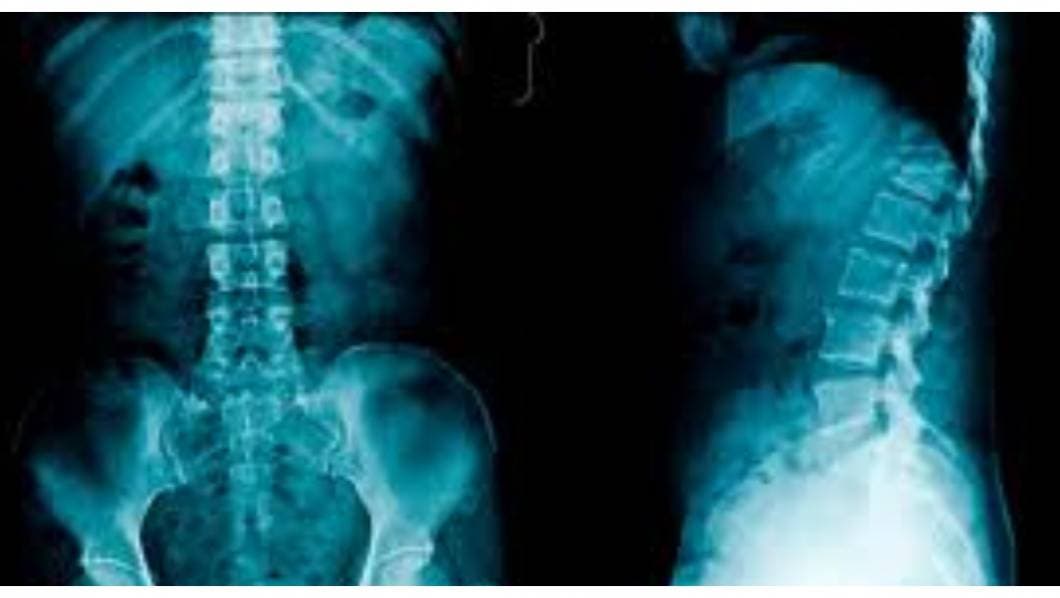

Las radiografías de la columna vertebralson imágenes de la columna vertebral. Pueden tomarse para detectar lesiones o enfermedades que afectan los discos o las articulaciones de la misma. Estos problemas pueden incluir fracturas, infecciones, dislocaciones, tumores, espolones óseos o enfermedad de disco en la columna vertebral.

También se realizan para revisar la curva de la columna vertebral (escoliosis) o para detectar defectos.

La columna vertebral está dividida en cuatro partes, de modo que hay cuatro tipos comunes de radiografías de la columna:

- Radiografía de la columna cervical. Esta prueba de radiografía toma imágenes de los 7 huesos del cuello (cervicales).

- Radiografía de la columna torácica. Toma imágenes de los 12 huesos del pecho (torácicos).

- Radiografía de la columna lumbosacra. Toma imágenes de los 5 huesos de la parte baja de la espalda (vértebras lumbares) y muestra los 5 huesos fusionados en la parte inferior de la columna vertebral (sacro).

- Radiografía del sacro/cóccix. Permite una visión detallada de los 5 huesos fusionados en la parte inferior de la columna vertebral (sacro) y los 4 pequeños huesos del cóccix.

Las radiografías de columna más comunes son de las vértebras cervicales (imágenes de la columna cervical [C]) y de las vértebras lumbosacras (imágenes de la columna lumbosacra [LS]).